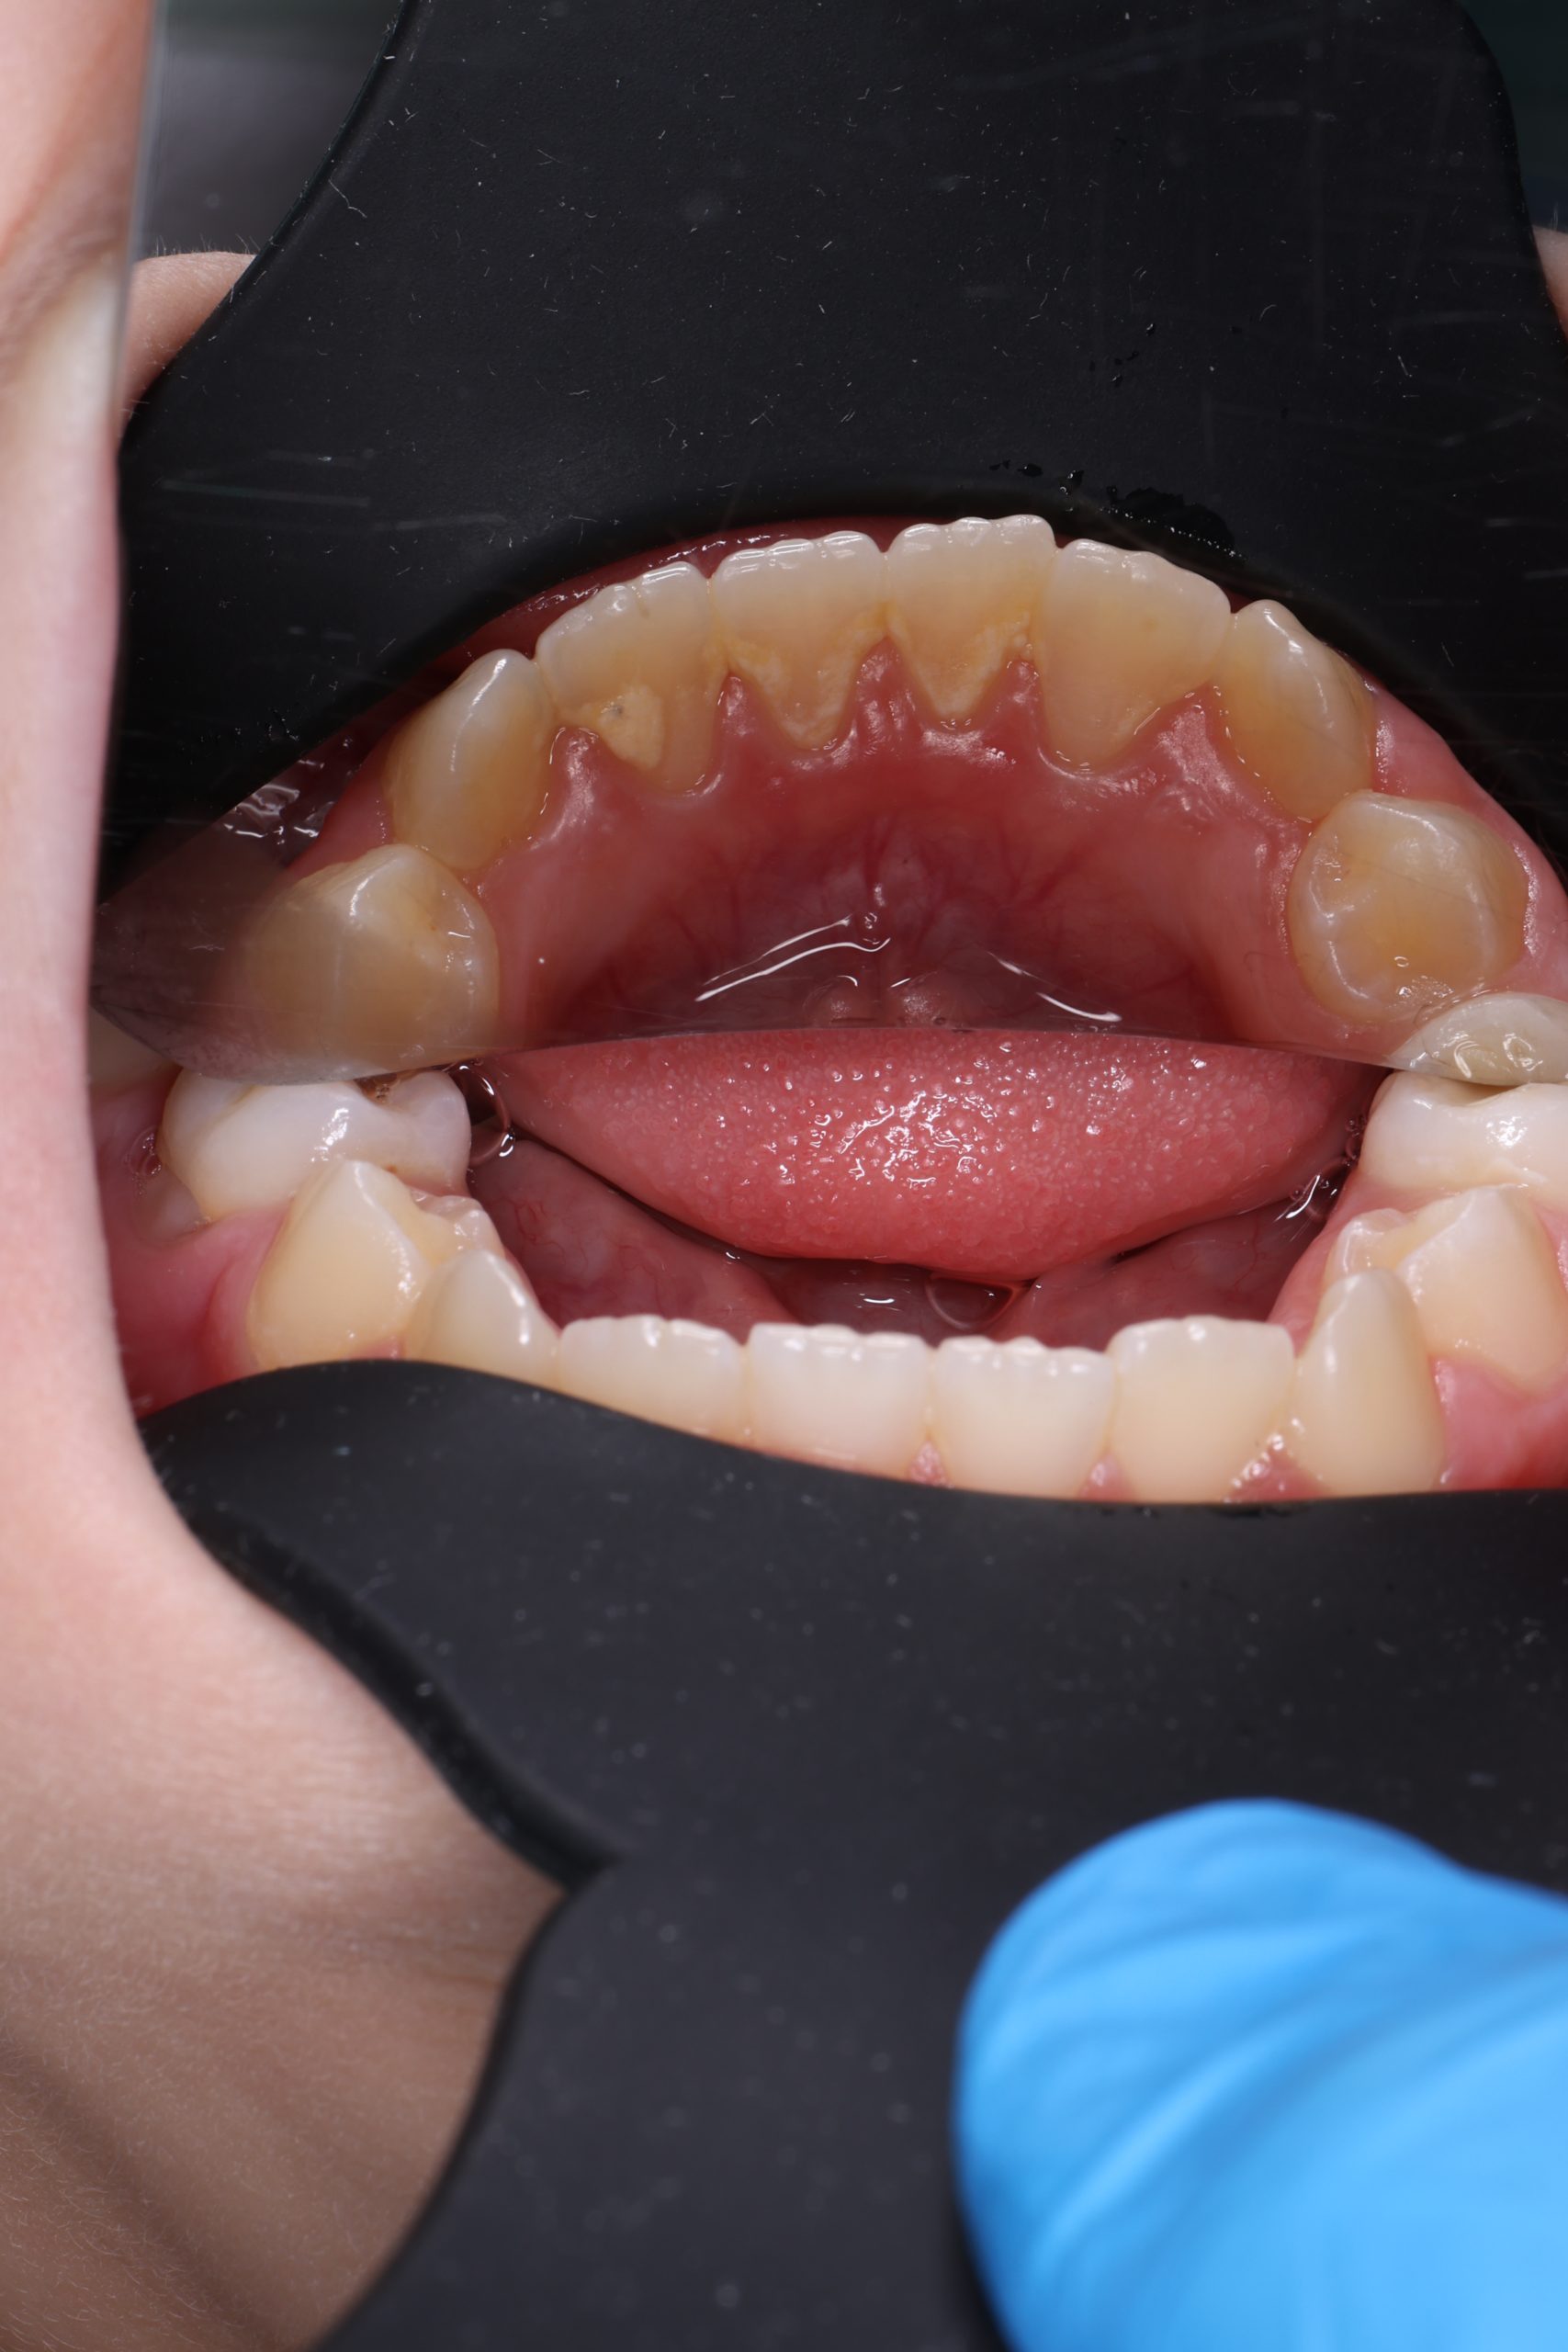

We examine the condition of teeth, gums, and bite. - Plaque Disclosure with Special Indicators

Areas that weren’t cleaned well appear purple. The darker the shade, the older the plaque. This helps both kids and parents understand where brushing needs to improve. - Brushing Training & Home Care Tools Selection